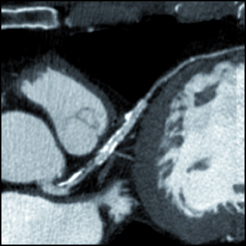

CT calcium scoring

There is mounting data showing CT coronary calcium scoring helps predict the risk level of cardiac patients.

There has been growing clinical evidence to show computed tomography (CT) coronary artery calcium scoring shows a close correlation with a person’s long-term risk for heart disease. This data convinced the American College of Cardiology (ACC) to include CT calcium scoring in its revised guidelines for prevention and cholesterol released last fall. In addition, the ACC highlighted the evidence for CT calcium scoring as a late breaking session at its 63rd Annual Scientific Session in March.

CT calcium scoring is a test that measures the amount and pattern of calcium that has accumulated in a patient’s coronary arteries. The test has been available for decades, but doctors and scientists debate whether and how it should be used to improve patient care.